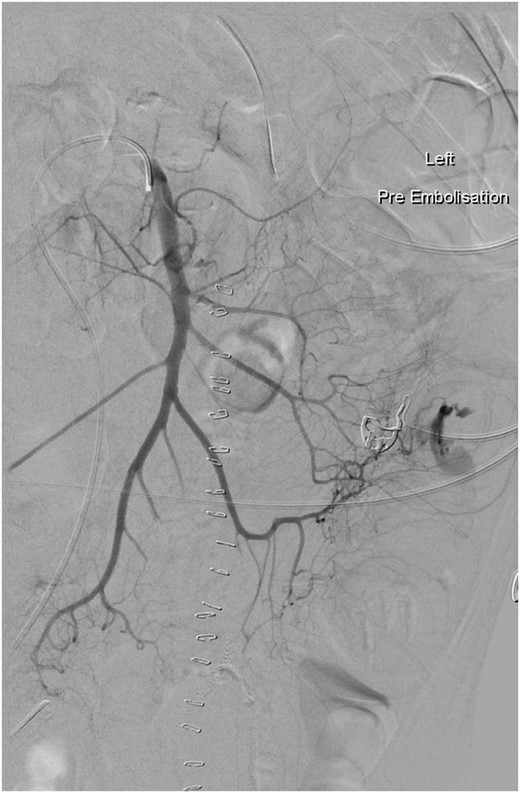

A week post-operatively he developed recurrent rectal bleeding. A colonoscopy, red blood cell (RBC) scan and CT angiography (CTA) were performed but failed to localize the site. Later that day he had further episodes of large volume rectal bleeding and a repeat CTA identified the jejunal anastomosis as the site of bleeding (Fig. 1). He underwent table endoscopy and re-laparotomy and the anastomosis was resected and the jejunum re-anastomosed. Post-operatively the bleeding settled and he was discharged home 2 weeks later.

Arteriogram showing active bleeding from branch of the superior mesenteric artery into the jejunum (arrowed), which was subsequently embolized.

Two weeks after discharge he commenced three agent chemotherapy (cyclophosphomide, vincristine, prednisolone). Approximately 10 h after this he developed severe abdominal pain and signs of peritonism. A CT scan showed free intra-peritoneal gas and a re-laparotomy was performed. Two spontaneous small bowel perforations were found proximal and distal to prior small bowel anastomosis and these were oversewn. On the fourth post-operative day he developed malaena and rectal bleeding. A CTA showed bleeding from a branch of the superior mesenteric artery, which was embolized with three tornado coils and haemostasis was achieved. A day later however he had ongoing rectal bleeding at which stage a decision was made not to perform any further interventions due to the poor prognosis and he subsequently passed away 3 days later.